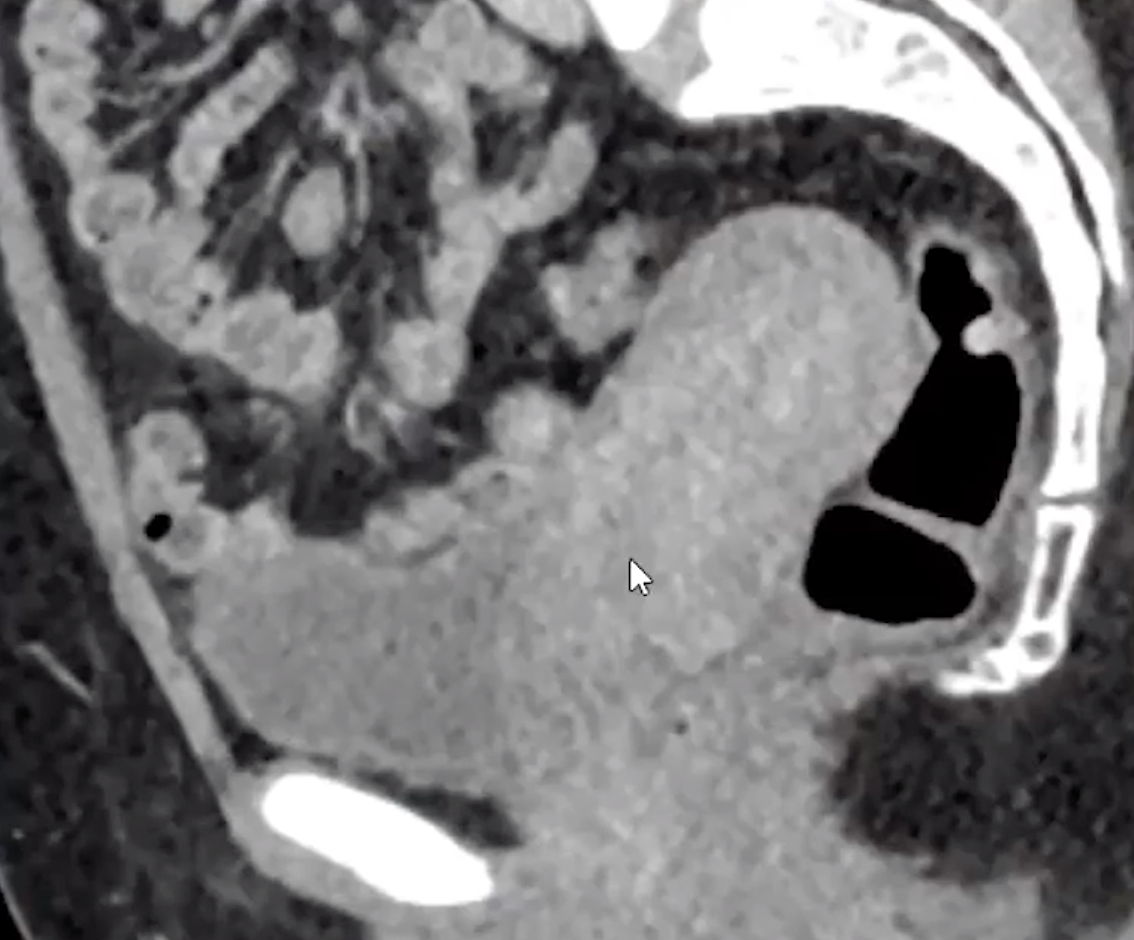

Dot-Dash sign seen with dermoid cysts

• Dermoid cyst = most common mass to cause

• Look for areas of increased echogenicity = fat

• Look for dot-dash sign = alternating echogenic dots and dashes = represents calcifications and hair